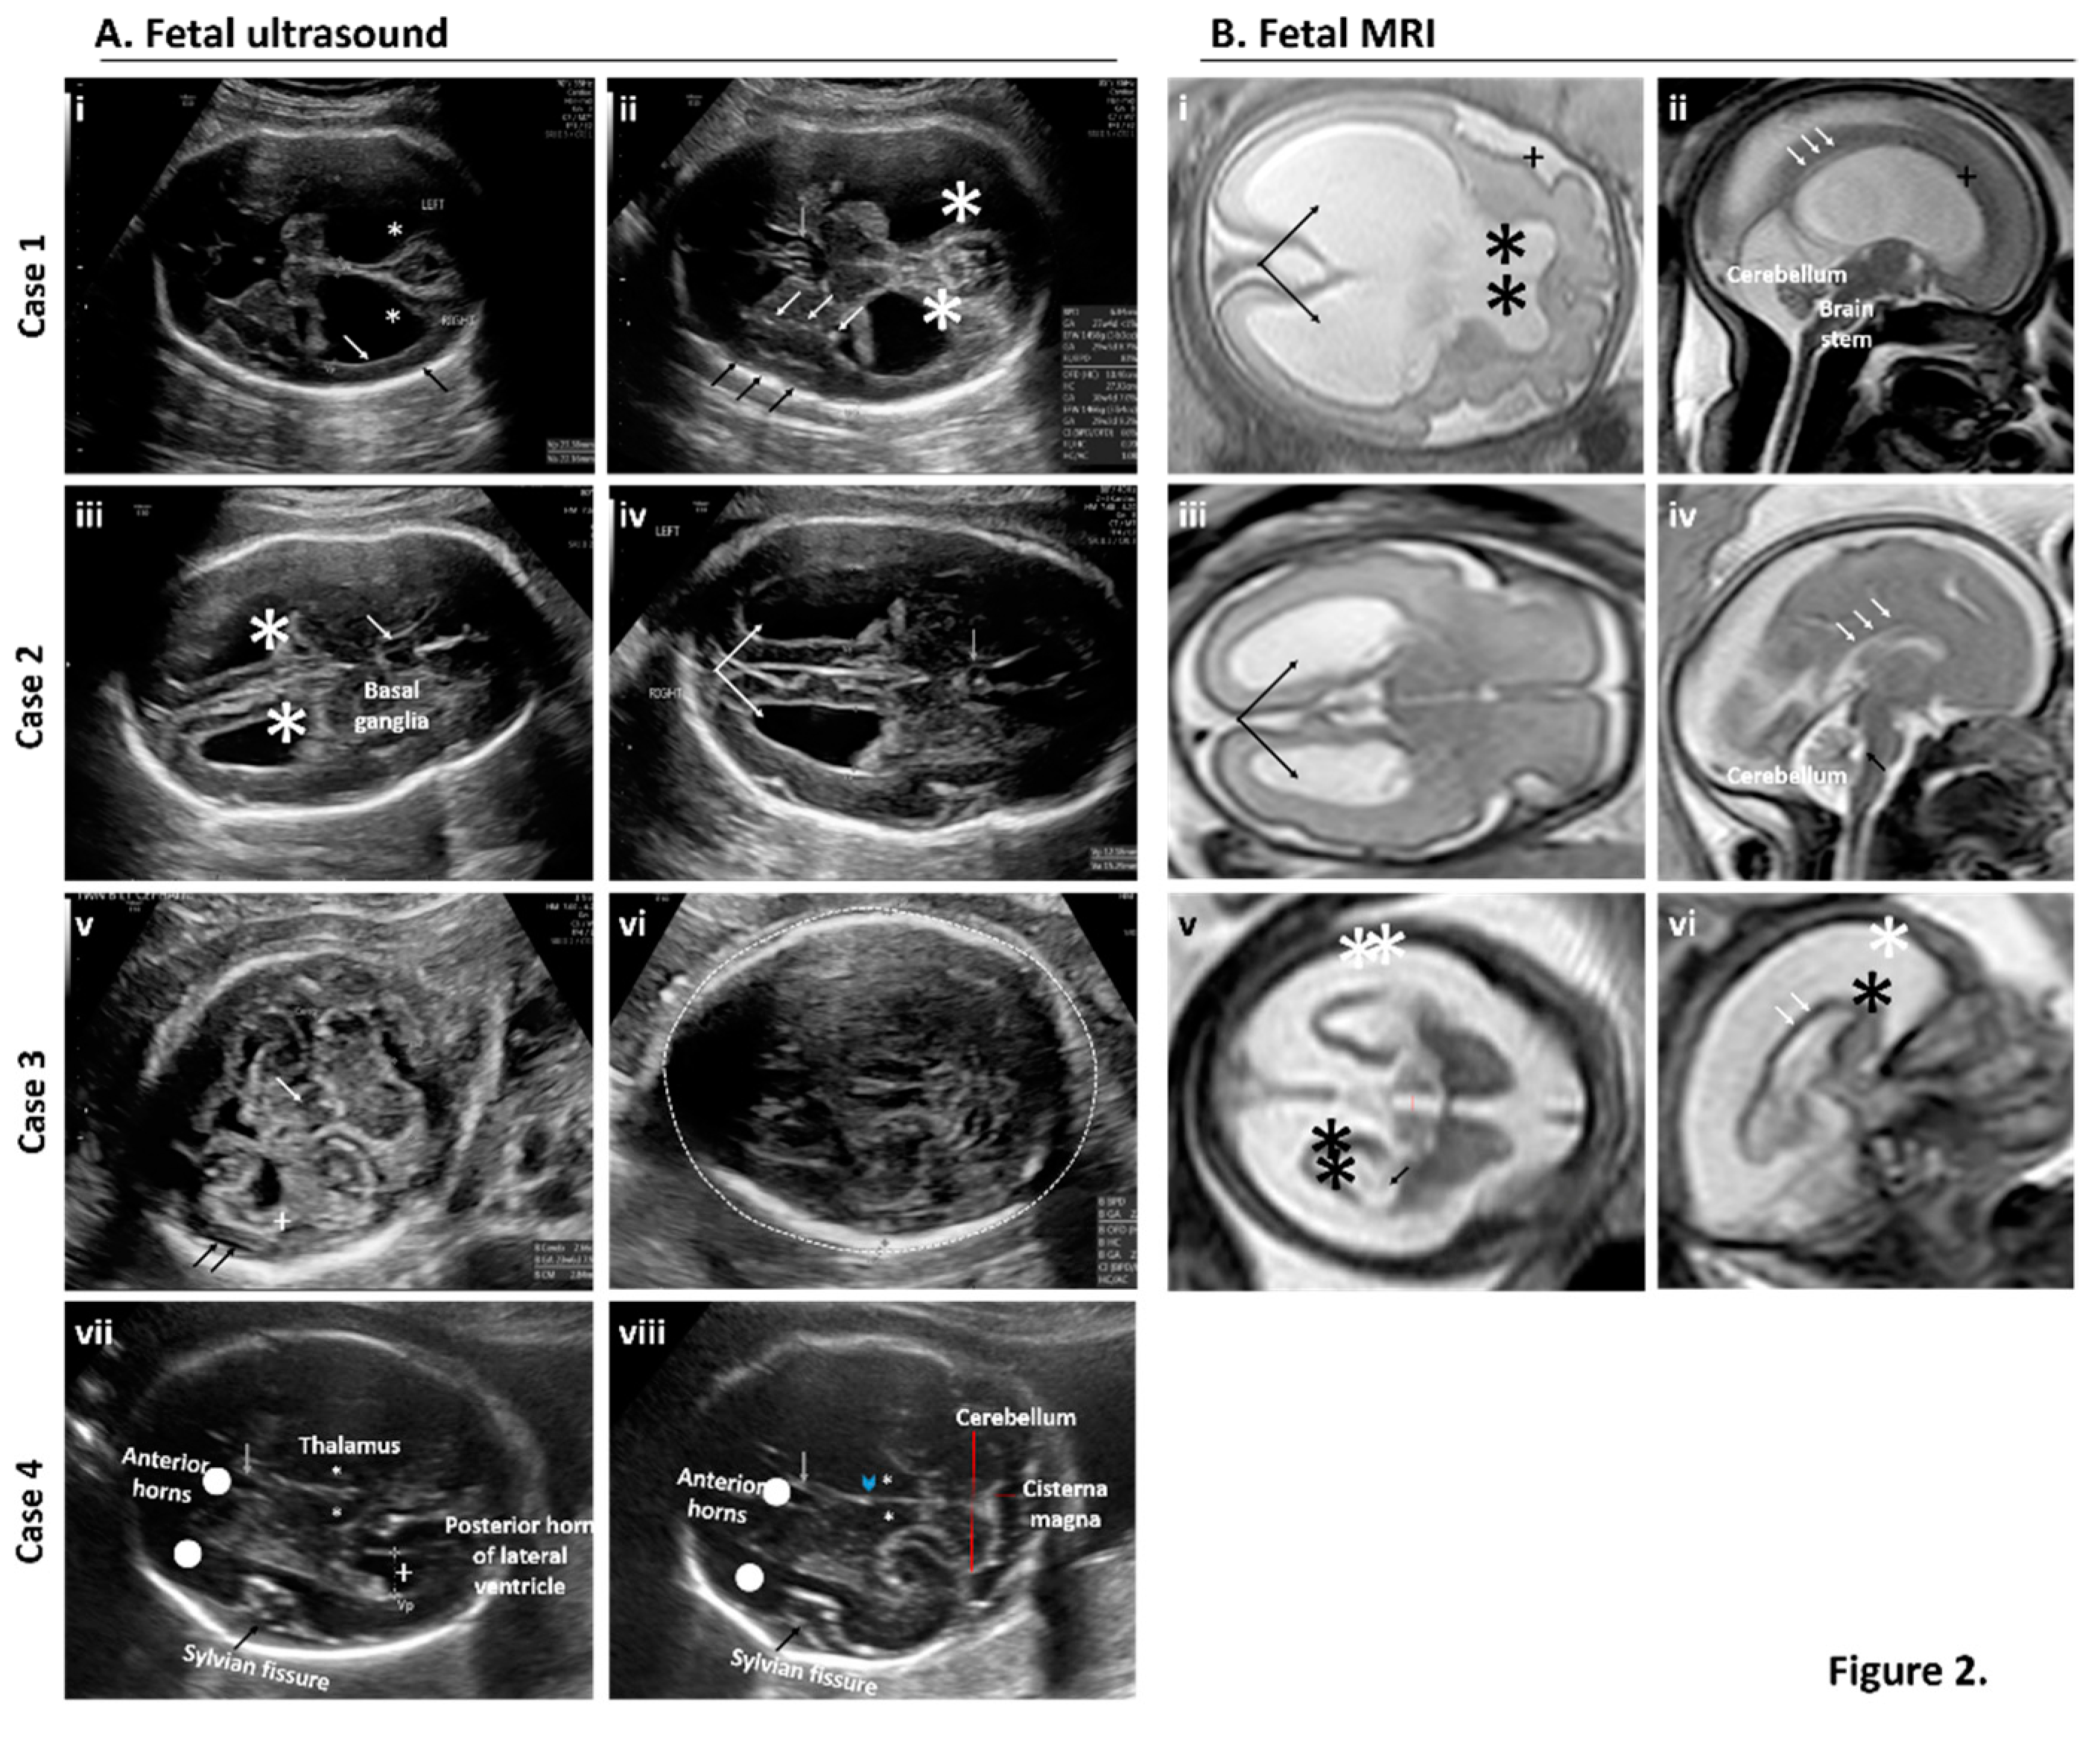

- Sanz Cortes, M.; Rivera, A.M.; Yepez, M.; Guimaraes, C.V.; Diaz Yunes, I.; Zarutskie, A.; Davila, I.; Shetty, A.; Mahadev, A.; Serrano, S.M.; et al. Clinical assessment and brain findings in a cohort of mothers, fetuses and infants infected with ZIKA virus. Am. J. Obstet. Gynecol. 2018, 218, 440. [Google Scholar] [CrossRef]